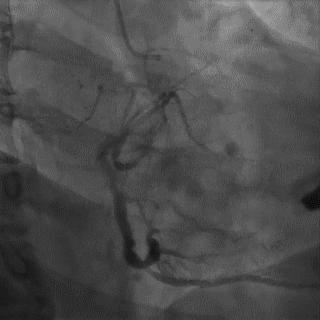

➢ CASE 1

➢ CASE 2

右冠起源异常,开口于左冠窦

➢ CASE 3

AL1.0

➢ CASE 4

➢ CASE 5

升主动脉造影未见桥血管显影,原位血管造影也没发现竞争血流迹象,可以确定桥血管已闭塞,必要时可以借助冠脉CTA辅助诊断